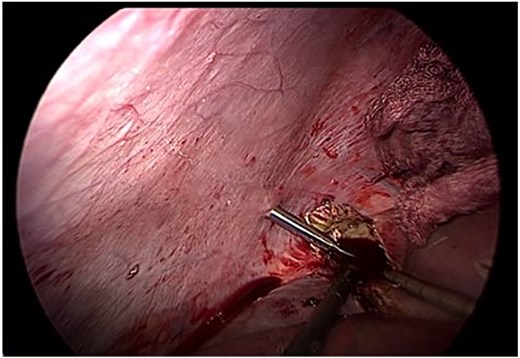

Following aspiration, the germinative membrane was carefully extracted using an endoscopic retrieval bag through a 10 mm trocar. The residual cavity was inspected with a 30° scope to detect any biliary communication (Fig. 3).

Endoscopic removal of the germinative membrane using an endobag through the 10 mm trocar. Inspection of the residual cavity was performed with a 30° laparoscope.

Given the size and location of the cyst, complete pericystectomy was not indicated due to proximity to major vascular structures and the absence of complications. Instead, careful evacuation of the membrane and limited resection of prominent pericystic tissue was performed, preserving liver integrity (Fig. 4). A drain was left in place due to the potential for undetected biliary communication.

Careful evacuation of cystic material and limited resection of prominent pericystic tissue. Complete pericystectomy was not indicated due to cyst size and location.